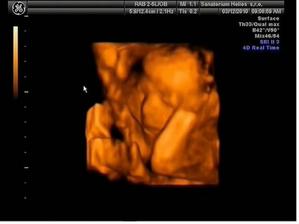

*17.2.10 ultrazvuk v 21tt + kardio ultrazvuk - vše úplně ukázkové :o) hurááá a vypadá to na holčičiku - první Dr. neviděl nic, byla zavrtaná prckou do měkkého a při vyšetření srdíčka se mrkl druhý pan Dr. i mezi nožky a říkal, že vidí holčičku, tak mu to budeme věřit :o) Večer manžel cítil kopanečky na bříšku, bylo to moc pěkný :o)